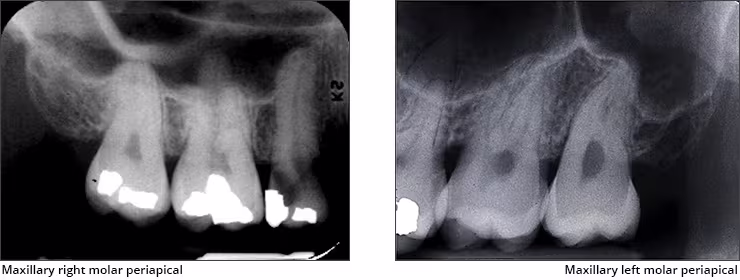

Maxillary sinus – The maxillary sinus is one of the paired paranasal sinuses. This prominent radiolucent air-filled cavity is located above the posterior teeth on the right and left sides of the maxilla (Figures 14 A&B). The sinus cavities are horizontally oblong bilateral structures with fine radiopaque borders. The maxillary sinus may contain septa which appear as radiopaque lines within the body of the sinus cavity. The size of the maxillary sinus can be quite variable and sometimes encroaches into the alveolar process, especially when posterior teeth are missing. Typically, the sinus appears uniform right to left. The maxillary sinus is sometimes referred to as the maxillary antrum and can be observed on both maxillary premolar and molar periapical images and partially on lateral-canine periapical images.

Figures 14 A&B: Maxillary Sinus